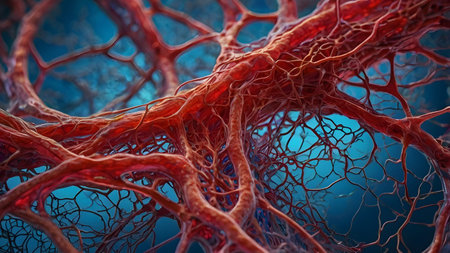

Macro view of human blood vessel network with red and blue tones showing capillaries and vein structure, ideal for illustrating medical anatomy and biology research.

Detailed visuals showcase the complex network of blood vessels in human anatomy.

A detailed view of red blood vessels intertwines across a soft gradient background. The intricate network showcases the complexity of human circulation highlighting the various sizes and shapes of the vessels

Vessel flow texture in red and blue lighting showing microscopic circulation system pattern symbolizing human biology, anatomy, and healthcare science visualization.

Detailed visualization of intertwined red capillaries resembling a biological network, set against a dark blue backdrop